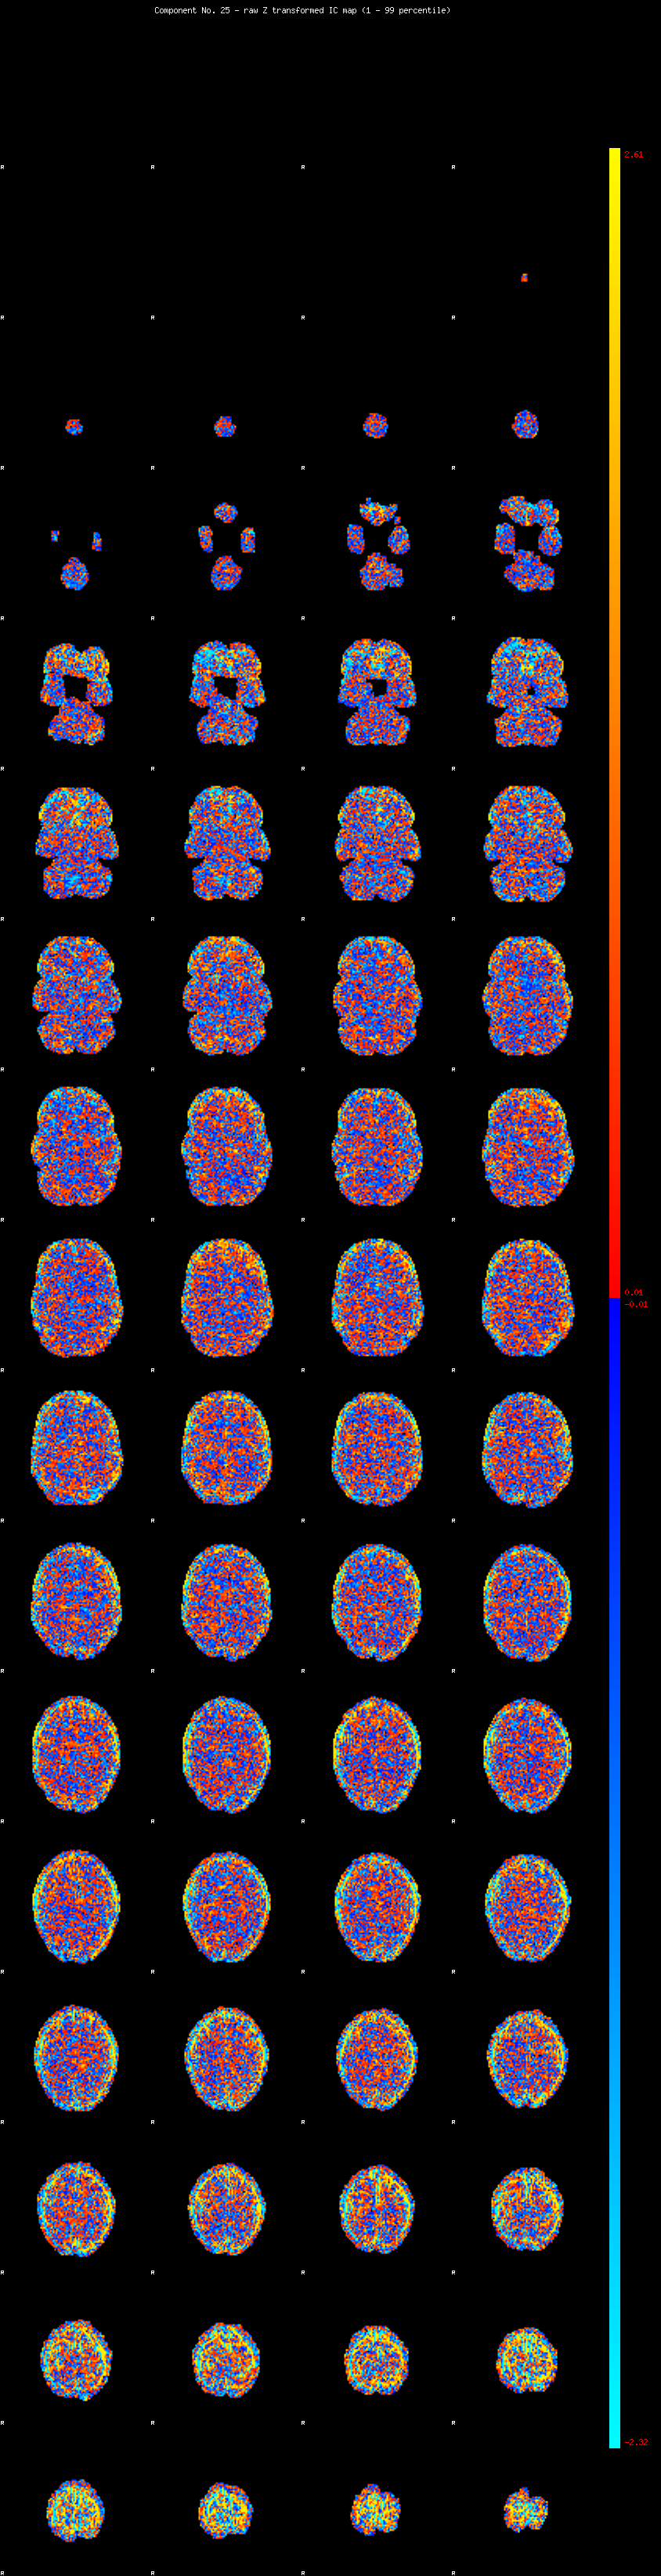

IC_25 Mixture Model fit

Means : 0.000000 2.807051 -2.562412

Vars : 1.000000 2.912548 2.151797

Prop. : 0.856403 0.080330 0.063267